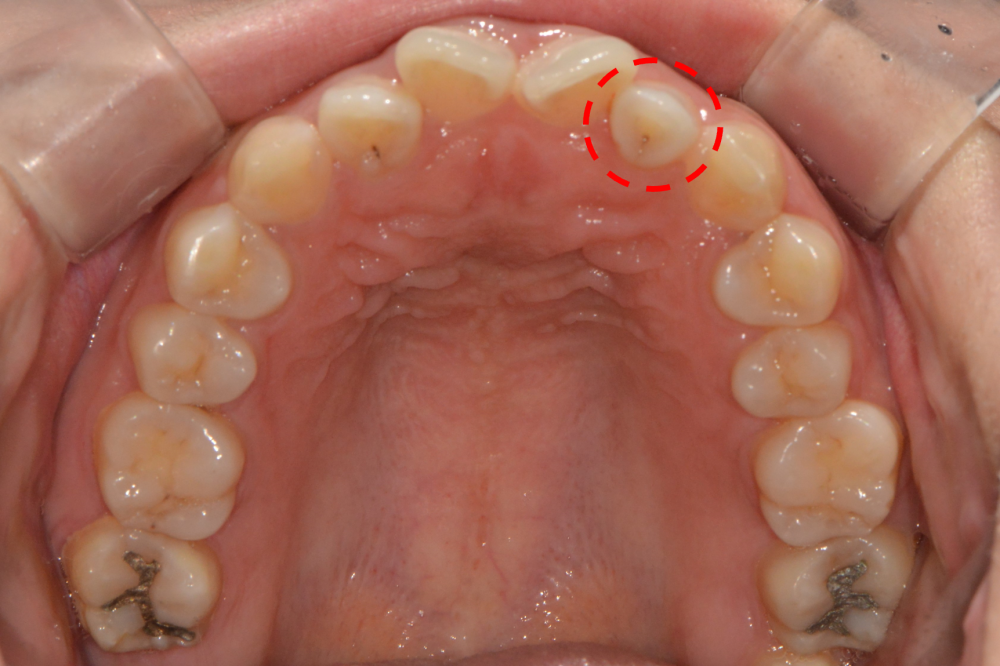

치아 표면에 움푹 들어간 홈이 있어요."

"겉으론 멀쩡해 보이지만 치아 속에서 조용히 문제가 일어나고 있을 수 있어요."

치내치(Dens in Dente)는 말 그대로 치아 안에 또 다른 치아 구조가 형성되는 기형적 형태를 말합니다.

이는 치아가 형성되는 과정에서 법랑질 기관이 비정상적으로 치아 내부로 함입되어 생기는 선천적 이상으로, 주로 상악 측절치에서 자주 발견됩니다.

겉으로 보기에는 치아가 정상처럼 보여서 환자분들이 스스로 알아차리기 어려운 경우가 많습니다.

** 치내치는 겉으로 드러나는 경우도 있지만, 많은 경우 X-ray나 CT 촬영을 통해 발견됩니다.

✔ 특정 치아 표면의 작은 홈에 음식물이 자주 끼거나 착색이 됨

✔ 겉으로 보이는 충치는 없으나 깊은 곳에 생긴 충치가 검게 비쳐 보임

약간의 충치가 진행된 상황이었으나, 다행히 깊이가 많이 깊지 않아서 간단한 레진 치료 후 교정 치료를 시작할 수 있었습니다.